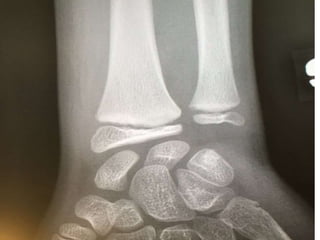

Diagnostic ?

A. Salter 1

B. Entorse cheville

C. Entorse haute

D. Salter 3

E. Avulsion

Fracture de Tillaux

• Salter 3

• Fracture de la portion latéral de

l’épiphyse du tibia distal

• La portion médiane de la physe du tibia

ayant déjà commencé à se fusionner

Conduite

• Atelle postérieure

• Référé 24 heures

• Aviser résident de garde ortho